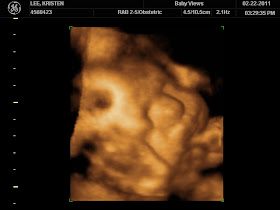

Yesterday, I had the joy of my life as I saw my baby boy - in color! Wow! Talk about an amazing experience! We watched for about 15 minutes as Nathan, (who was trying to sleep, poor thing), kicked and jerked and hid his face from us. After rolling MYSELF around and poking my own stomach, he finally moved his hands and we saw his little face - a mirror of Grant, in my opinion. We spent 45 minutes in awe of what God has done. To think that He took a portion of me and a portion of my husband and created a new life, and then placed that life inside my womb. How can anyone not believe in such a BIG, awesome, mighty, and powerful God?!

Nathan is currently 4 lbs and 11 ounces and 17 inches long. In the words of the sweet lady who did our ultrasound, "He is perfect." Not a hint of any problem. He will most likely be born weighing 7-8 lbs and around 19-20 inches long.

What to see our little man?  *big smile*